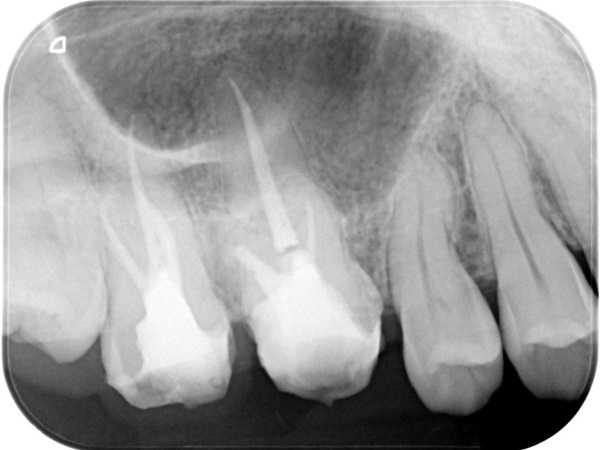

根管治療終了時

根管治療終了後3か月経過